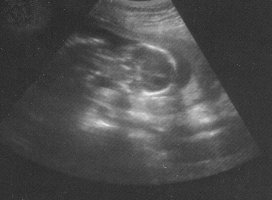

Heute war ich wieder Baby gucken, alles bestens. (TH= 11.71 und CAP 3,75, beide Werte entspr. 17+3). Krümel liegt quer zur Zeit, Kopf rechts und Beine links)- geschätzte Länge von Knirps/Knirpseline zwischen 15-20 cm

Heute wurde die Diagnostik bezgl. "Offener Rücken" gemacht. US soweit unauffällig, Blutergebnisse folgen bis Montag.

Bild folgt später. Mein Doc will immer noch nicht gucken, was es denn nun wird, werde langsam ärgerlich.

Ich war ja auch bei der VU und unserem Bauchzwerg geht es blendend. Er war so aktiv, dass es einfach nicht möglich war, ein normales Bild zu bekommmen.